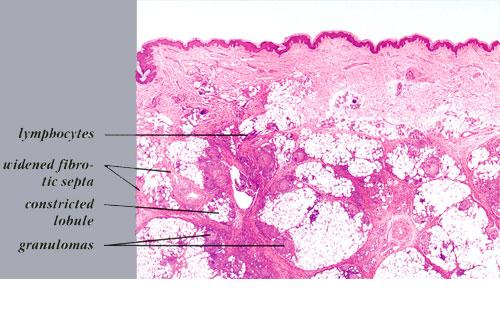

Histopathology. The histologic changes are present mainly in and near the septa of the subcutaneous tissue .

. The overlying dermis often has only a minimal to moderate, superficial and deep perivascular lymphocytic infiltrate.

Later lesions of acute erythema nodosum show widening of the septa, often with fibrosis and with inflammation at the edges of the septa and involving the periphery of the fat lobules . Neutrophils usually are absent, and the vascular changes are less prominent than in early lesions. There are more macrophages in the infiltrate. Macrophages at the edges of the fat lobules show phagocytosis of lipid from damaged adipocytes, and the small droplets of lipid in their cytoplasm give them a "foam cell" appearance. Granulomas formed by macrophages, without lipid deposition, are more frequent

when late lesions are compared with early ones . The granulomas often are loosely formed with macrophages predominating in a focus with multinucleated giant cells. Occasionally, well-formed, discrete sarcoidal granulomas occur in small numbers in the septa. The multinucleated cells usually have an irregular distribution of the nuclei in the cytoplasm. The oldest lesions have septal widening and fibrosis with a decrease in all of the inflammatory cells.